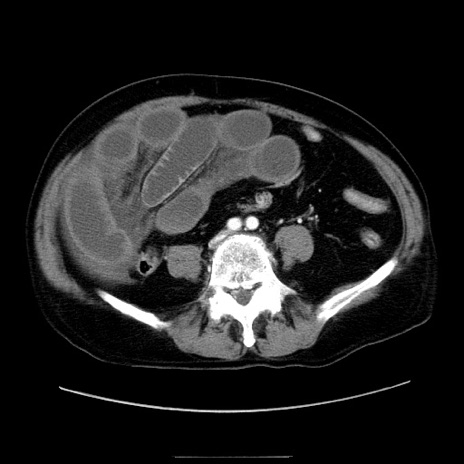

症例30(横断像)

【症例】80歳代男性

【主訴】臍周囲痛

【現病歴】約6時間前から臍下部痛が出現。次第に腹部膨隆・背部痛も生じてきたため来院。背部痛の場所は変化しない。

【身体所見】意識清明、BT 36.3℃、BP  131/87mmHg、P 87bpm、SpO2 100%(RA)、臍周囲自発痛・圧痛あり、反跳痛なし、自発痛部位に一致して板状硬あり、腹部膨隆、腸雑音減弱、CVA tenderness両側陰性。